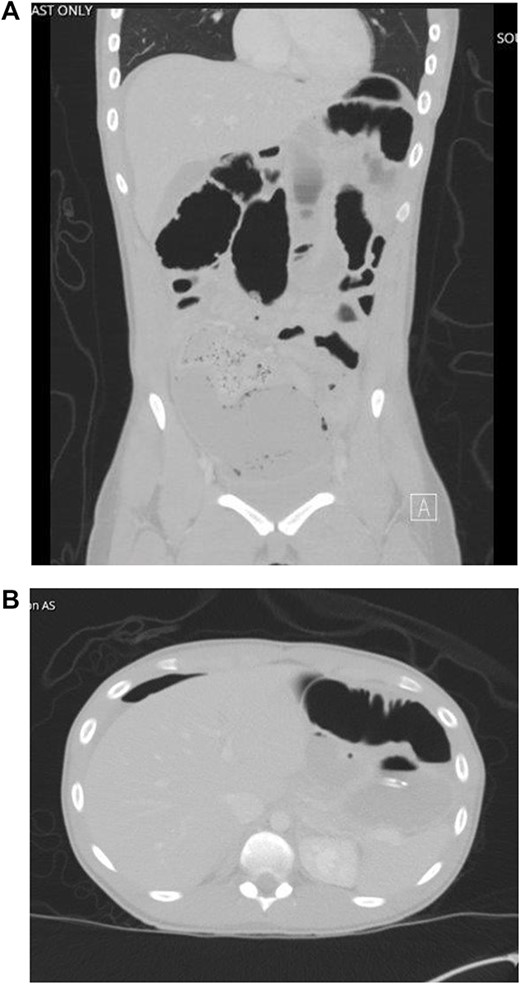

The patient was tolerating a diet, and experiencing anterograde bowel function on postop Day 9; however, the decision was made to obtain a CT of the abdomen pelvis due to an increasing leukocytosis shift. CT revealed two fluid collections with gas pockets, anteriorly measuring 4.0 × 2.8 cm, 9.8 × 6.3 cm in the rectal space (Fig. 3).